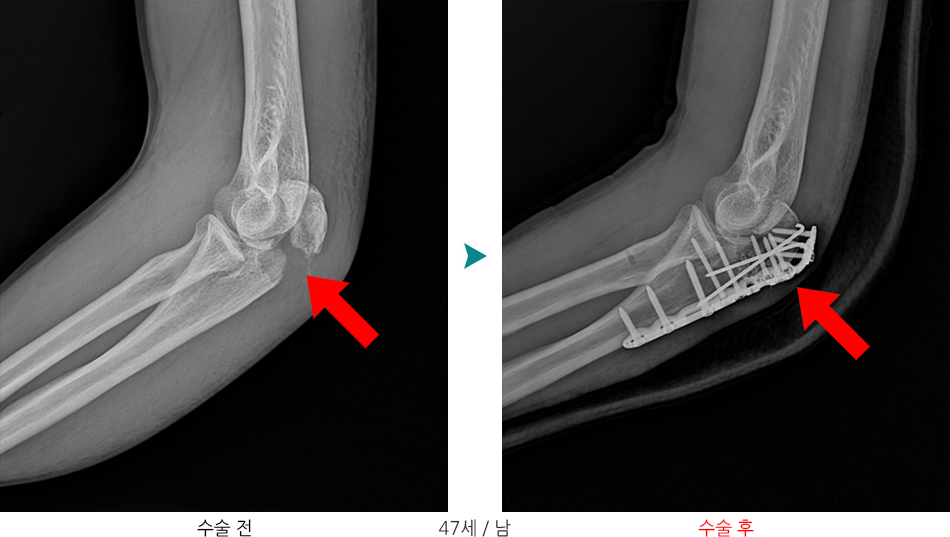

요골두골절과 구상돌기골절이 동반된 주관절 탈구는 주위 연부조직과 골조직에 심한 손상을 주는 복합손상으로 측부인대 손상이나 관절 불안정성이 흔히 동반되며 적절한 치료를 받지 않을 경우 합병증으로 만성관절 불안정성, 관절강직, 이소성 석회화 및 외상 후 관절염등이 흔히 발생하기 때문에 예방을 위해서는 적절한 치료와 재활이 필요하며, 적절한 치료를 받지 못하거나 치료시기를 놓치는 경우 팔꿈치 인공관절 전치환술을 시행해야하는 상태로 이어질 수 있습니다.

※ 구상돌기 골절의 경우 단독손상은 드물며, 주관절 탈구와 요골두 골절과 동반되어 발생하는 경우가 가장 흔합니다. 축성압박 및 외반력에 의해 척골 근위부와 요골두가 회외전하며 상완골과 탈구되고, 이때 상완골 활차(상완골 하단의 중앙이 약간 패인 관절면)에 의한 충격에 의해 구상돌기 골절이 발생하게됩니다.

1형의 경우 보존적치료를 시행하며, 2,3형의 경우 관혈적 정복술 후 내고정술을 시행하게됩니다.